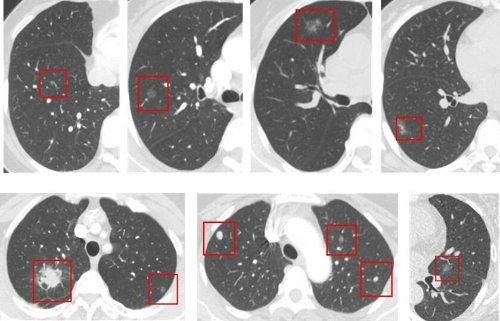

近日,国家药品监督管理局经审查,批准了杭州深睿博联科技有限公司生产的创新产品“肺结节CT影像辅助检测软件”的注册。

该产品物理组成包括安装光盘和加密狗,逻辑组成包括客户端软件、Web端软件及服务器软件。该产品用于胸部CT影像的显示、处理、测量和分析,可对4mm及以上肺结节进行自动识别并分析结节影像学特征,。 同时属于人工智能医疗器械软件,基于深度学习技术的基本框架,可实现肺结节的自动检出。在保证肺结节检出准确性满足临床需求的基础上,提高检出效率,减轻医师工作量。